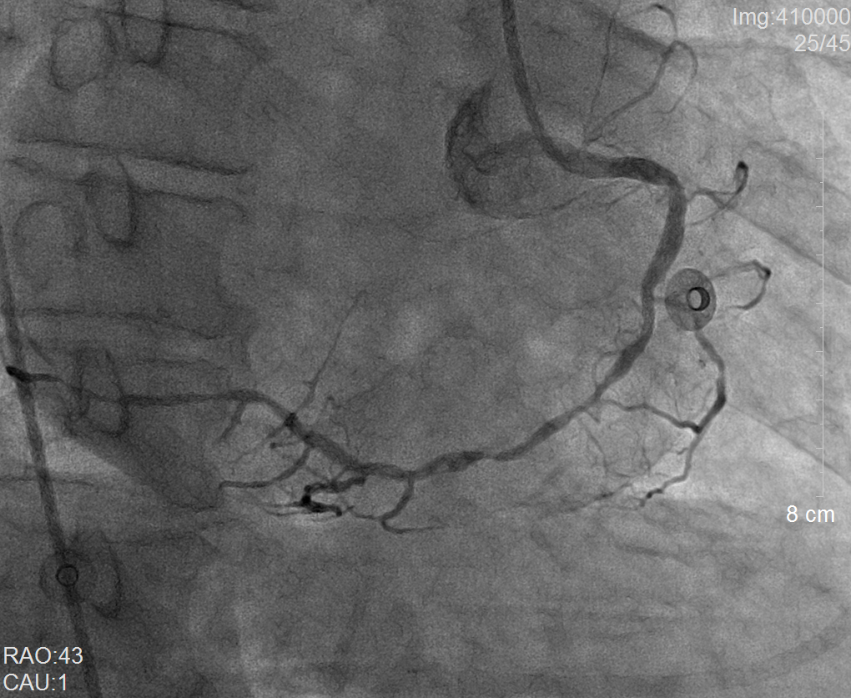

术前冠脉造影提示右冠状动脉弥漫性病变                 术后冠脉造影提示右冠状动脉血流通畅